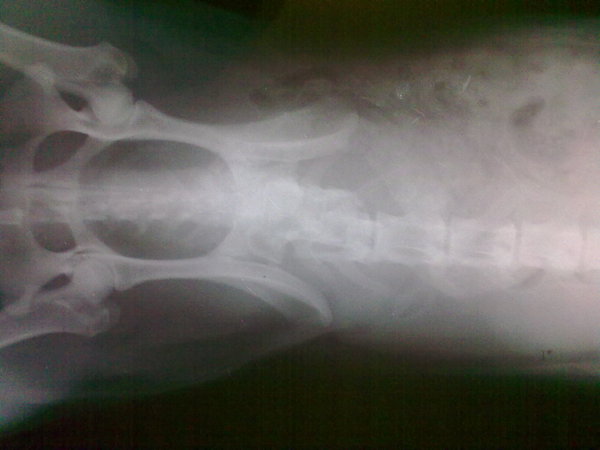

Вложения:

24082010160.jpg

24082010160.jpg [ 363.9 КБ | Просмотров: 58860 ]

И наркоту лопает так же, димедрол и фенозепам каждый день. А так же катозал, кетофен, травматин и фуросемид.

Меня удивляет как он при таком вставать умудрялся.